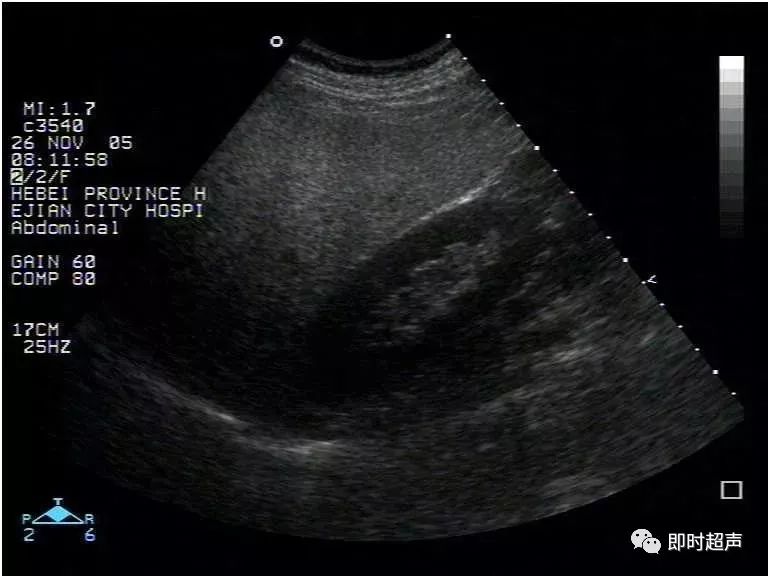

超声表现:

1、肝实质回声细密增强,呈云雾状,后方回声衰减。

2、肝内管道结构显示欠清。

3、肝肾对比阳性,正常情况下肝脏回声略高于肾实质回声,脂肪肝时肝脏回声明显增强。

4、肝脏增大,形态饱满,边缘变钝。

轻度:肝回声增强,后方回声衰减不明显,肝内管道结构显示正常。

中度:肝回声明显增强,后方回声衰减,肝内管道结构显示欠清晰。

重度:后方回声衰减明显,后方肝组织显示不清,膈肌显示不清。